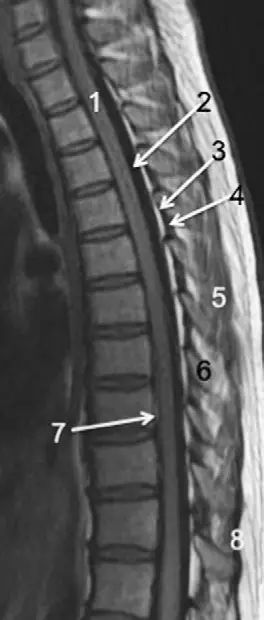

脊柱的MRI解剖